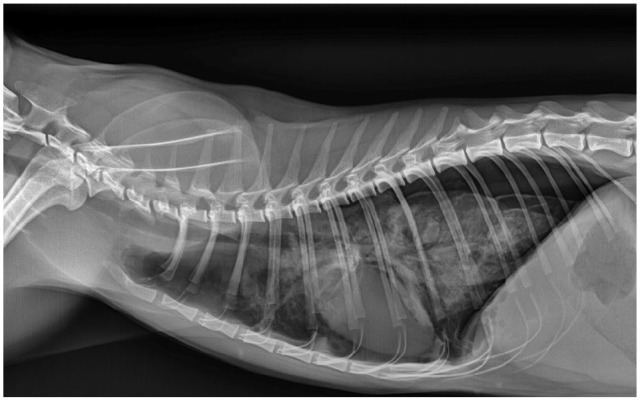

病例总结:一只1岁的完整雌性家养短毛猫,因呼吸窘迫和呼吸急促加重而接受评估。这只猫在4天前被主要临床医生诊断为自发性气胸,并接受了治疗性胸穿刺治疗。在体格检查中,患者表现出肺音减少,呼吸急促和呼吸力度增加。复发性自发性气胸经胸片证实,并重复治疗性胸穿刺。胸穿刺后肺超声显示肺实变、肺结节及多发囊肿样病变,回声壁不规则增厚,中心无回声。胸部重复x线片显示弥漫性中度支气管间质型伴多灶性软组织结节。彻底的粪便检查显示卵子与肺吸虫种类相似,随后的分子分析证实了威氏肺吸虫。猫最初仅用芬苯达唑治疗,结果改善有限,自发性气胸复发。芬苯达唑联合吡喹酮的第二个疗程导致临床改善。这只猫没有任何临床症状,病情很好,在诊断后2年的胸片上没有可识别的肺结节。相关性和新信息:本报告描述了一种新的囊肿样肺超声发现,其特征是回声壁不规则增厚,中心无回声,伴有P westermani感染,表现为复发性自发性气胸。该报告还强调了一种成功的治疗方法,可以长期解决问题。这种新的肺部超声发现的识别有助于早期诊断和治疗猫的肺吸虫感染,特别是对那些出现呼吸窘迫和气胸的猫。

Case summary: A 1-year-old intact female domestic shorthair cat presented for evaluation of worsening respiratory distress and tachypnoea. The cat had been diagnosed with spontaneous pneumothorax 4 days earlier by the primary clinician and treated with therapeutic thoracocentesis. On physical examination, the patient exhibited decreased lung sounds, tachypnoea and increased breathing effort. Recurrent spontaneous pneumothorax was confirmed via thoracic radiography, and therapeutic thoracocentesis was repeated. Lung ultrasound performed after thoracocentesis revealed lung consolidation, pulmonary nodules and multiple cyst-like lesions with irregularly thickened echogenic walls and anechoic centres. Repeat thoracic radiography showed a diffuse moderate bronchointerstitial pattern with multifocal soft tissue nodules. A thorough faecal examination revealed ova resembling those of Paragonimus species, and subsequent molecular analysis confirmed Paragonimus westermani. The cat was initially treated with fenbendazole alone, which resulted in limited improvement and recurrent spontaneous pneumothorax. A second course of fenbendazole combined with praziquantel led to clinical improvement. The cat remained free of clinical signs and was doing well, with no identifiable lung nodules on thoracic radiography 2 years after diagnosis.

Relevance and novel information: This report describes a novel cyst-like lung ultrasound finding characterised by an irregularly thickened echogenic wall and anechoic centre, associated with P westermani infection in a cat presenting with recurrent spontaneous pneumothorax. The report also highlights a successful treatment approach resulting in long-term resolution. The identification of this novel lung ultrasound finding can facilitate early diagnosis and treatment of Paragonimus species infection in cats, especially for those presenting with respiratory distress and pneumothorax.